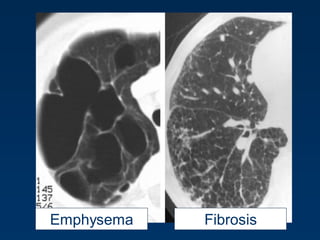

Emphysema typically presents as

areas of low attenuation without

visible walls as a result of

parenchymal destruction.

EMPHYSEMA

Permanent, abnormal enlargement of air

spaces distal to the terminal bronchiole

and accompanied by the destruction of

the walls of the involved air spaces.

Combined Pulmonary Fibrosis and Emphysema

The combination of emphysema in the upper lobes and fibrosis in the

lower lobes (CPFE) is being increasingly recognized as a distinct entity in

smokers .

Patients are almost exclusively men in their 6th and 7th decades.

Lung volumes are relatively preserved despite markedly impaired diffusion

capacity and hypoxemia during exercise.

Honeycombing, reticular opacities, and traction bronchiectasis are the

most frequent findings at high-resolution CT in the lower lungs, while the

upper lungs exhibit paraseptal and centrilobular emphysema